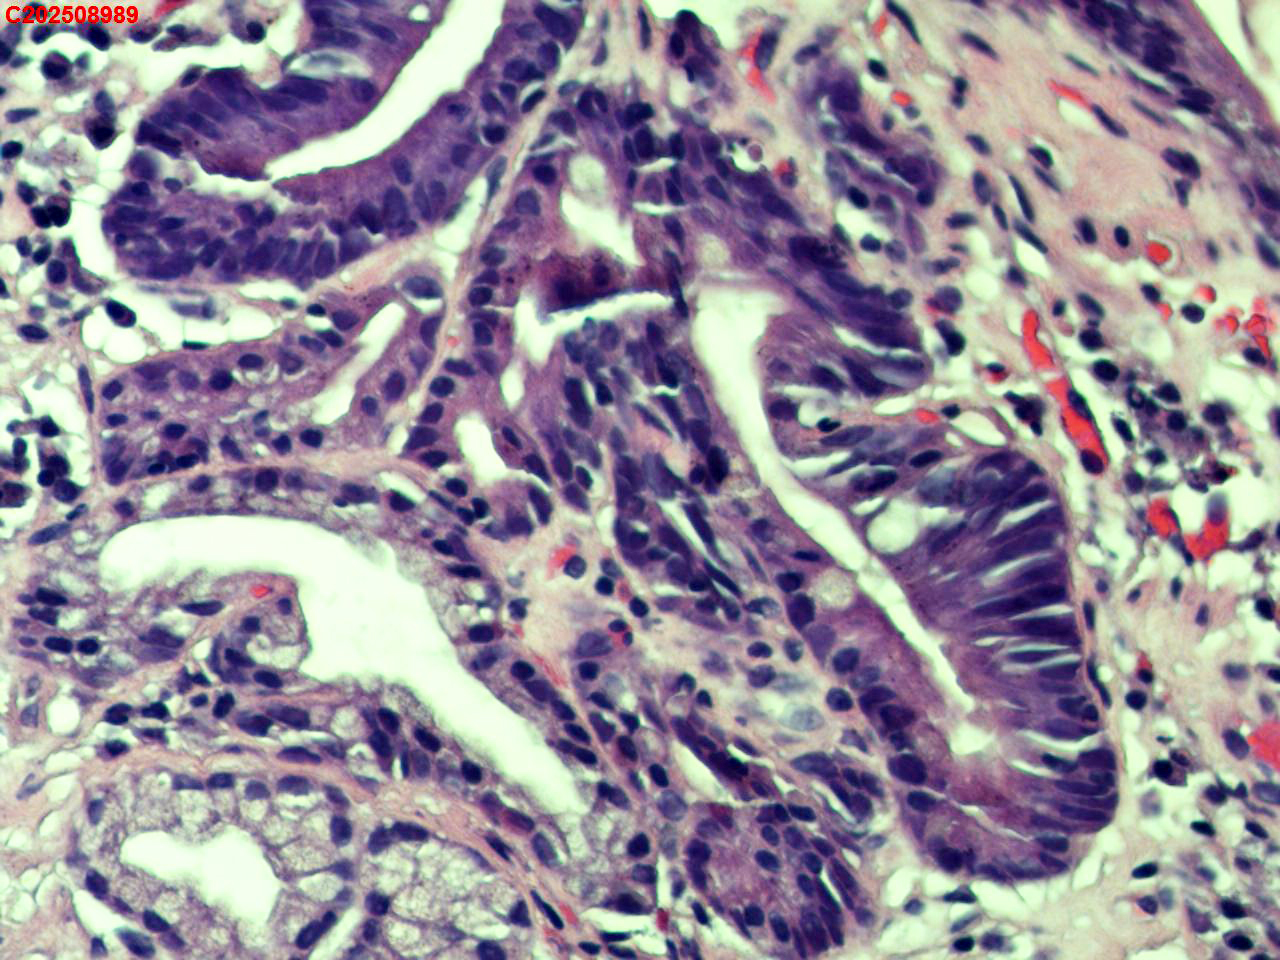

胃窦粘膜

性别

女

年龄

62岁

临床诊断

慢非萎伴糜烂

一般病史

体检

标本名称

大体所见

胃窦多发充血、糜烂。

萎缩+肠化+糜烂+修复

萎缩及糜烂

慢性萎缩性炎,伴肠化。